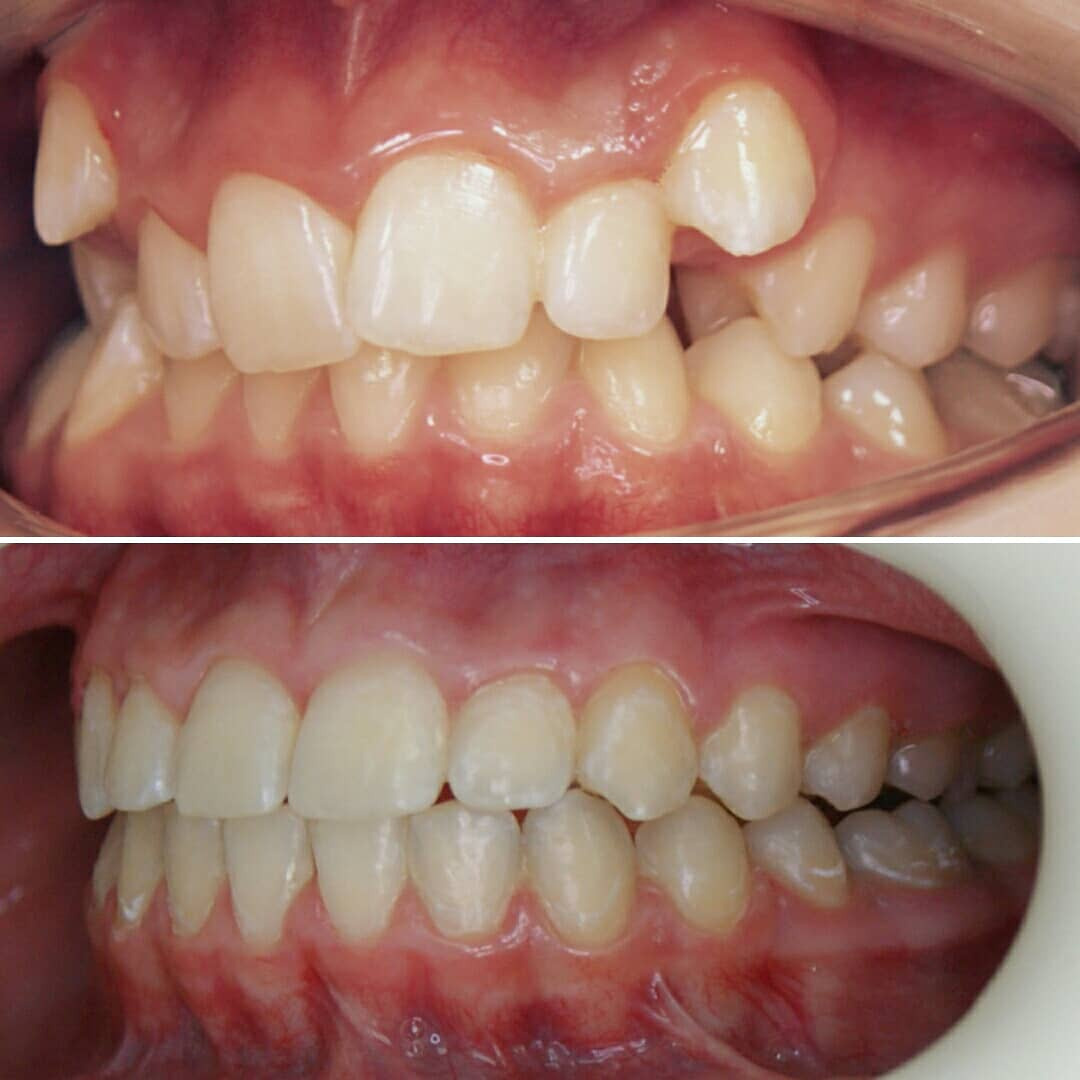

🔷️ Промежуточный результат лечения на аппарате Марко Роса (6 месяцев). Пациенту 7 лет. Самое удивительное - как "отвечает" на лечение нижняя челюсть: расширяется, меняется её положение и корректируется дистальный прикус, выравниваются нижние зубы, хотя никаких аппаратов на нижней челюсти не было!

P.S. Каждый случай уникальный, чаще нижнюю челюсть мы всё таки расширяем тоже.